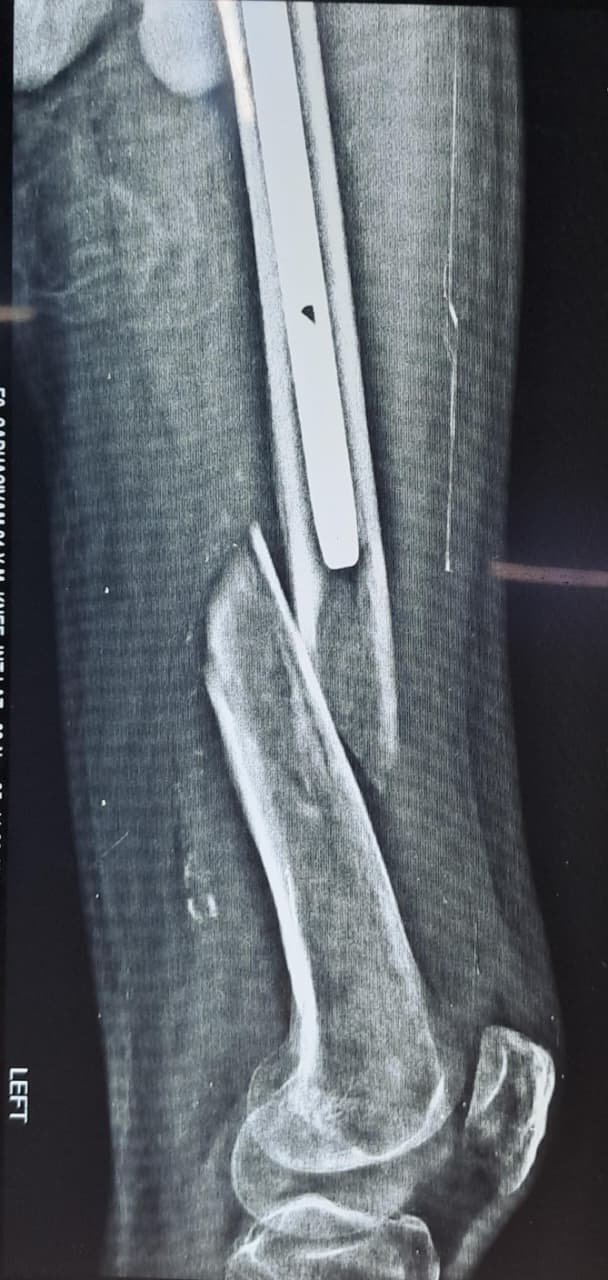

Peri-implant fracture

Atlas ID: 4 • Orthonotes Atlas

Peri-implant Fractures

Peri-implant fractures - Case Based Discussion